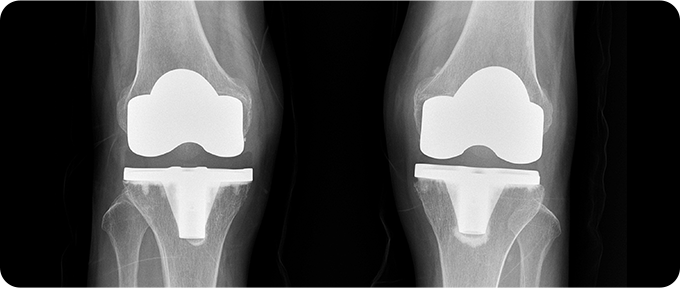

말기 - 인공관절 수술

손상된 관절을 제거하고 인공 관절로 대체하여 통증을 완화하고 관절 기능을 회복하는 치료법입니다. 이 수술은 주로 말기 퇴행성 관절염 환자에게 시행되며, 관절의 심한 변형과 극심한 통증을 해결하는 데 효과적입니다. 수술 과정은 손상된 연골과 뼈를 제거한 후, 금속과 플라스틱으로 만들어진 인공 관절을 삽입하는 방식으로 진행됩니다.